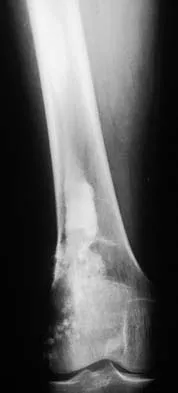

Figures 32a and 32b show the AP and lateral radiographs of an 11-year-old boy who has a severe limp, a fever, and swelling and tenderness of the thigh. Aspiration of the bone reveals purulent material. The patient has most likely been symptomatic for

In patients with an osteomyelitic infection, radiographic findings at 1 to 5 days usually show soft-tissue swelling only. Seven to 14 days after symptoms begin, radiographs will most likely show the classic signs of acute osteomyelitis. Reactive bone formation would be expected by 6 months. Kasser JR (ed): Orthopaedic Knowledge Update 5. Rosemont, IL, American Academy of Orthopaedic Surgeons, 1996, pp 149-161.